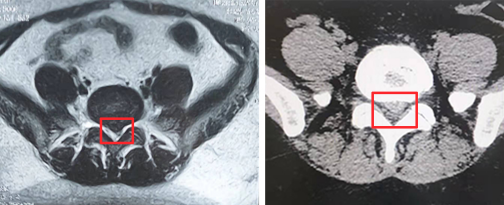

我院脊柱科张冶副主任医师详细查阅了柳女士的病史资料并完善相关检查后,确诊她为腰椎间盘突出症伴腰椎椎管狭窄,且神经压迫严重,有明确的手术指征。在了解到柳女士惧怕“开大刀”的诉求后,张冶医生建议采用我院常规开展的微创手术,单边双通道脊柱内镜技术(UBE)行椎间盘切除。

“单边双通道脊柱内镜属微创手术,优点就是创伤小、出血少、并发症少,术后恢复快,基本上第二天患者就可以下床活动了。”张冶医生介绍UBE时说,与传统开放手术相比,该手术仅需在患者后背切开两个约1cm大小的创口,然后借助人体天然解剖间隙建立微创工作通道,通过内窥镜可以清晰的显露神经根及突出椎间盘。该手术方法对椎旁肌肉损伤较小,避免伤及神经根及硬膜囊,能够较大程度地保留完整的脊柱结构,保持腰椎的稳定性和完整性。